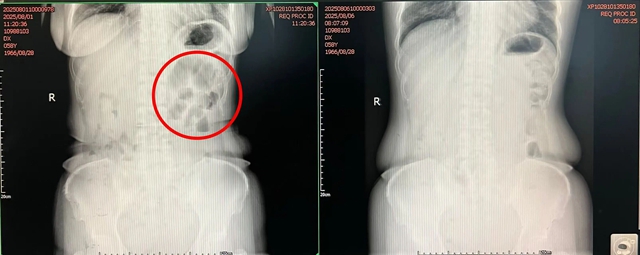

转院后的第一时间,我院立刻启动多学科会诊机制。周阿姨的腹部X光片上,左上腹的肠管像充了气的气球鼓鼓囊囊,一段段液体与气体分隔的影子清晰可见,像一声声急促的提醒——病情已不容迟疑。

继续治疗一周后复查,腹部平片上那片鼓胀的积气已基本消失,困扰她一个月的肠梗阻竟已基本解除。

患者治疗前后X片对比图